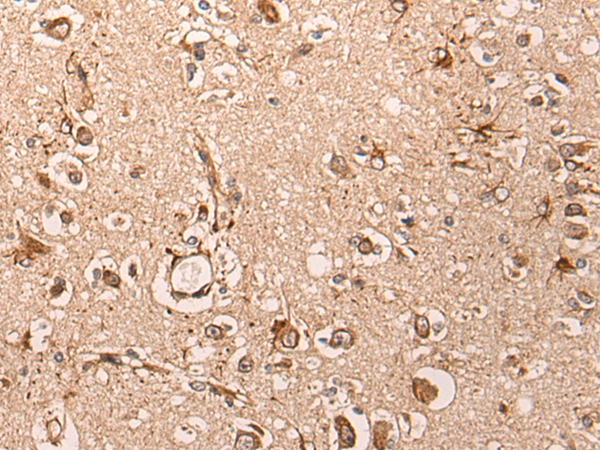

The image on the left is immunohistochemistry of paraffin-embedded Human brain tissue using 46603(MAFB Antibody) at dilution 1/30, on the right is treated with synthetic peptide. (Original magnification: x200)